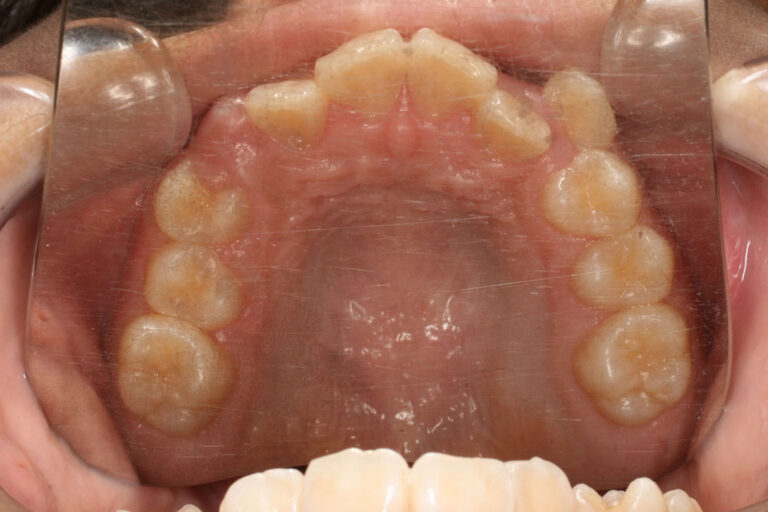

上下顎前歯部に重度の叢生(がたつき)がある患者さんです。 小児矯正で側方拡大してもスペースが足らないほどがたつきの強い場合、または小児矯正を始める時期が遅かった場合、将来的に無理に非抜歯で治療を続けると、前歯は前方に傾斜して並んでしまいますので上顎前突または上下顎前突のような仕上がりになってしまいます。 この患者さんは、小児矯正で1年ほど歯列の側方拡をしたのち、マルチブラケット装置での動的治療を開始しました。 早く終わりたいと言う意志が強く、歯ブラシ、顎間ゴムの協力もとても良かったです。 マルチブラケット装置での動的治療期間2年1か月でした。 | ||